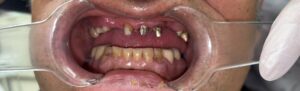

写真をご覧ください。

真ん中2本の歯のない所に、両横から橋を伸ばして6本の歯を作ります。

前歯のブリッジです。自然で、よく噛めるようになられました。